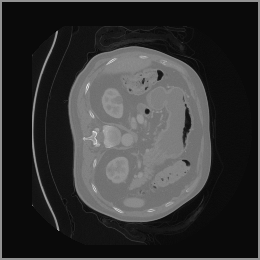

To demonstrate the advantages of 3D semantic image synthesis over 2D semantic semantic image synthesis, we conducted a detailed comparison with the SegGuidedDiff [26] model. SegGuidedDiff generates medical images based on 2D semantic maps, producing individual 2D slices that are later stacked to form a 3D image. However, this approach has limitations in capturing spatial continuity and coherence across slices, which is critical for representing the spatial structure of 3D medical images. As a result, inconsistencies often arise between different slices, particularly in preserving anatomical structures across the coronal and sagittal planes. The generated images exhibit varying levels of denoising, resulting in differences in brightness and sharpness across the images. This inconsistency in denoising can lead to noticeable variations in visual quality, where some regions appear clearer and others less distinct.

As shown in Figure 5, the generated slices exhibit high consistency across adjacent slices. The anatomical structures and semantic patterns are smoothly and coherently preserved between slices, indicating that our model is capable of generating 3D-consistent synthetic images rather than isolated 2D slices.

In our approach, we employ a compression factor of 4 to encode 3D medical images into the latent space. This level of compression reduces the spatial resolution of the original image (e.g., from 256×256 to 64×64 per slice), while still preserving the essential anatomical structures and semantic content. The latent representation at this scale offers a favorable trade-off between dimensionality reduction and semantic fidelity. Specifically, although fine-grained textures are simplified, key structural patterns (e.g., organ boundaries, lesion shapes) remain visually distinguishable and semantically coherent. As the compression rate increases, the latent representations become progressively more abstract. With lower compression (e.g., 2× or 4×), the latent features preserve key anatomical structures and spatial layouts, making them beneficial for our semantic image synthesis task in latent space, as the model can operate on compressed representations that retain sufficient semantic information without being overwhelmed by high-frequency noise. In contrast, higher compression rates (e.g., 8× or above) lead to a loss of fine-grained details and reduced semantic fidelity. The choice of a 4× compression thus ensures that the latent features are compact and meaningful, facilitating effective conditional generation while significantly reducing computational overhead. We therefore adopt a 4× compression as a compromise between computational efficiency and semantic preservation. The corresponding 2D slices in image space and latent space are shown in Figure 7.

Figure 8 further supports these findings: the images generated by Med-LSDM preserve spatial coherence across coronal and sagittal planes, whereas those from SegGuidedDiff show noticeable inconsistencies. These artifacts likely result from the 2D nature of SegGuidedDiff, which fails to account for 3D spatial relationships. In contrast, our model’s volumetric diffusion framework inherently preserves anatomical consistency, highlighting its advanta in synthesizing high-fidelity 3D medical images.